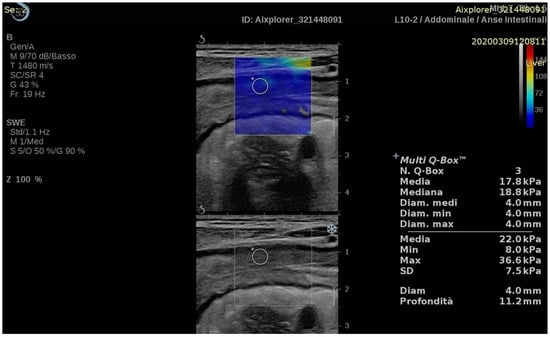

| Chen (2018) [29] | CD | Stricture characterization | Prospective (35) | Aixplorer, SuperSonic Imagine | 2D-SWE | 2D-SWE values were higher in severe fibrosis compared to mild or moderate fibrosis (23.0 ± 6.3 vs. 17.4 ± 3.8 and 14.4 ± 2.1 kPa, p = 0.008). | Histology |